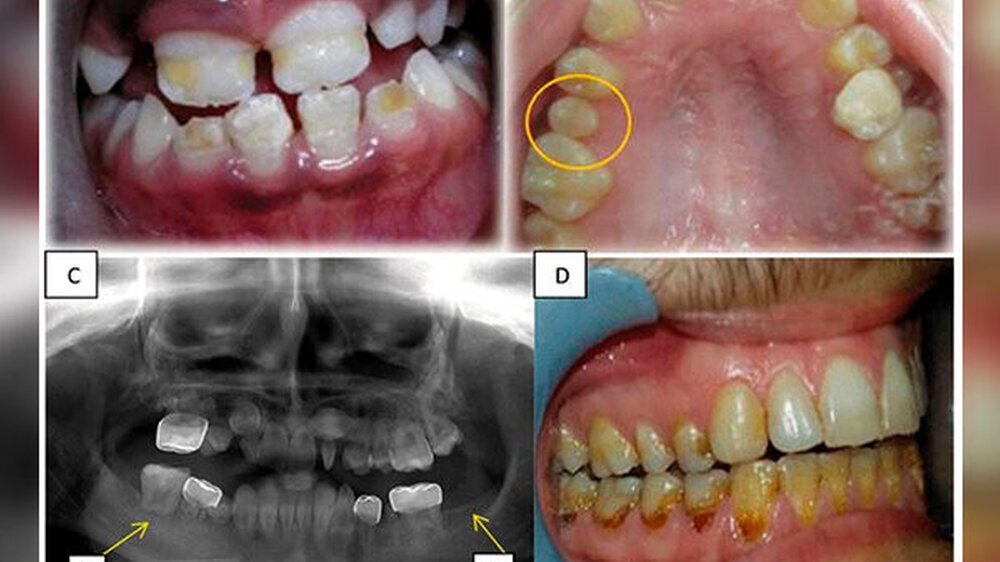

Der Studie zufolge sind die ersten Anzeichen von Zahnentwicklungsstörungen frühestens zwei Jahre nach der Krebsbehandlung zu erwarten. Zu den dokumentierten Anomalien gehörten Hypomineralisierung, Hypoplasie, Mikrodontie und Hypodontie. Zahnwurzelanomalien waren die am häufigsten auftretende Veränderung.

Darüber hinaus gab es auch Fälle von übermäßiger Retention von Milchzähnen, Impaktion, vorzeitigem Durchbruch, verminderter Beweglichkeit des Kiefergelenks, Kieferklemme und Gesichtsdeformitäten. Die signifikantesten geschlechtsspezifischen Unterschiede bei den Zahnanomalien war eine höhere Inzidenz von Mikrodontie bei den Mädchen und eine höhere Prävalenz kariöser Zähne bei den Jungen.